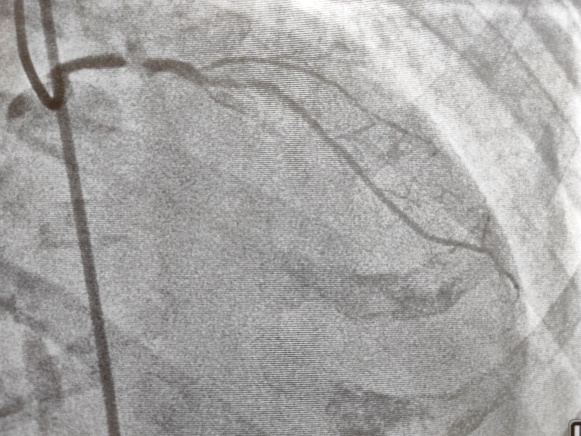

术前造影提示前降支回旋支均闭塞

图片

术后造影提示血管开通,血流恢复